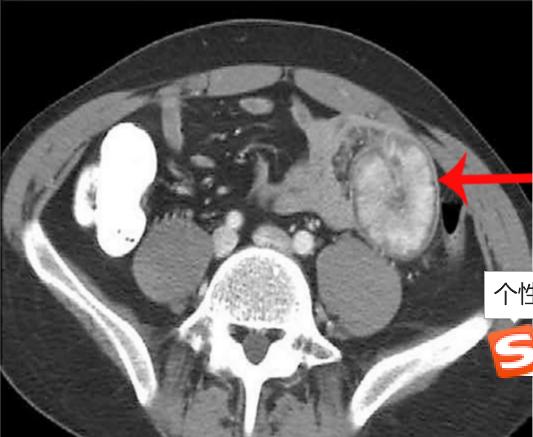

彩超和腹部CT对诊断肠套叠有较高的诊断率。肠套叠的腹部CT表现一般为软组织肿块影,常呈现"同心圆征"或"靶环征",有时称假肾征。有时肠管套入部较深,可表现为"双肠管征"。

假肾征